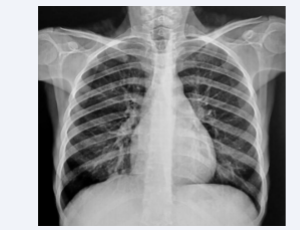

AbstractTakayasu’s vasculitis is a rare chronic inflammatory arteritis of unknown origin affecting large arteries in young subjects. We report the observation of a 32-year-old female patient who presented for 6 months with dyspnea stage II mMRC associated .....